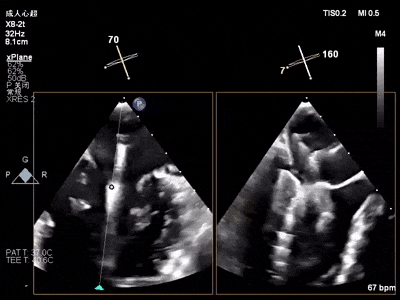

术中超声(关键步骤)

术前心超

混合性MR,P2脱垂连枷(脱垂范围15mm,连枷间距4mm),腱索断裂

新分型:ACA型,反流2区及两侧,MR 4+,VC:3×14mm

A2:24mm,P2:17mm,AP:38mm,MVA约5.7cm²